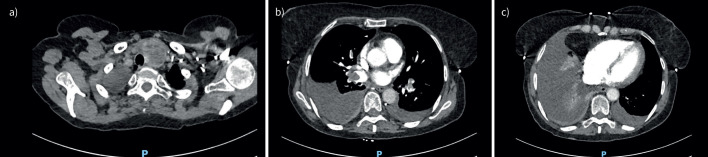

Bilateral pleural effusions, ascites and pulmonary emboli: Meigs syndrome.

Meigs syndrome is associated with unilateral or bilateral pleural effusions, ascites, high CA-125 levels and ovarian fibromas. Concurrent arterial and venous thromboses have also been described. Surgical removal of the fibroma is curative. https://bit.ly/4jZsB4D.